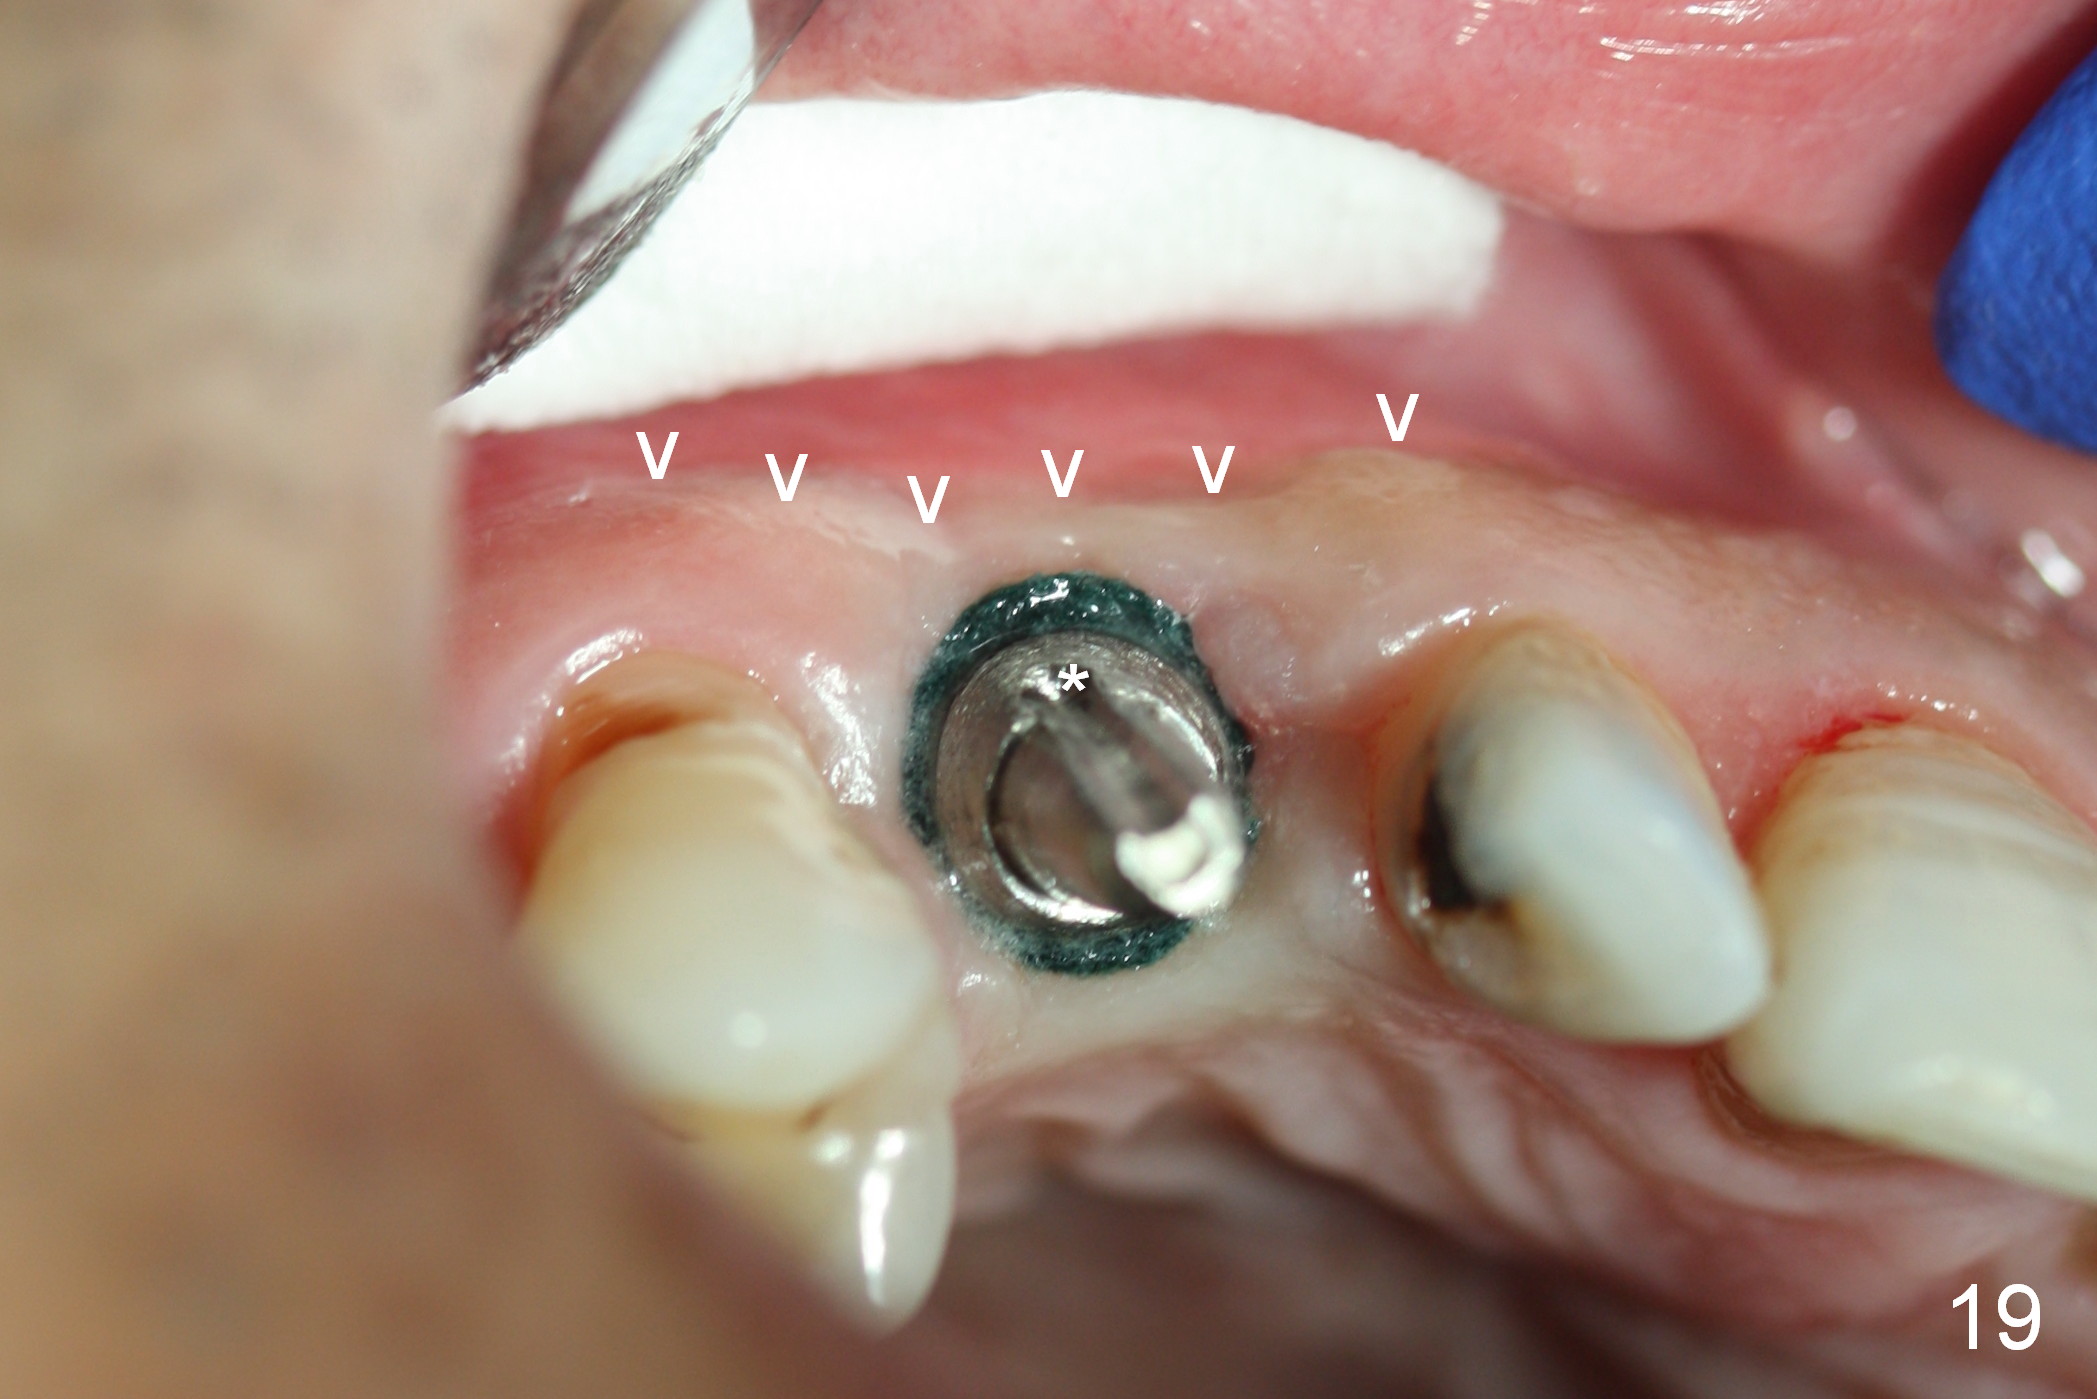

One and a half months later (3 months postop), the patient returns for final crown impression. The buccal gingiva has grown coronally (Fig.17 arrow). The implant appears to have osteointegrated (Fig.18). The buccal plate has become concave (Fig.19 arrowheads). To maintain the gingival level, the buccal portion of the implant/abutment (Fig.19 *) is going to be reduced (Fig.20 *). The margin of the definitive restoration will be at the prep margin and thin so that the gingiva is expected to continue to be growing coronally after cementation.